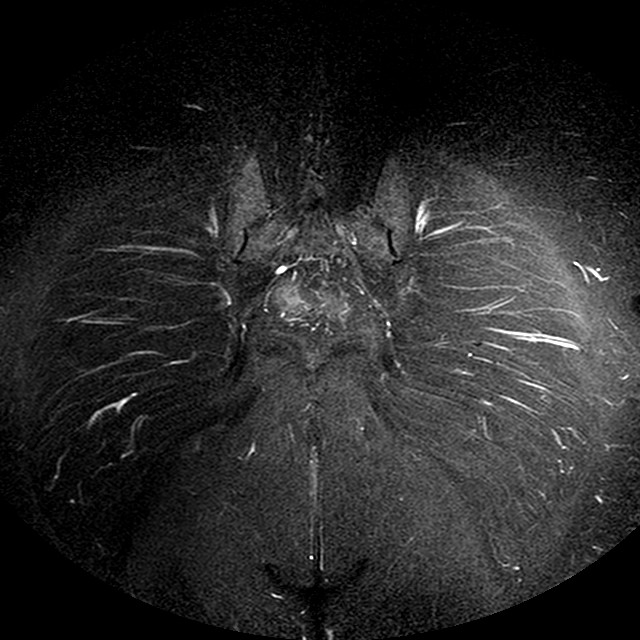

STIR

Evidenti e simmetriche alterazioni osteofitosiche in regione coxo femorale con riduzione delle rime articolari. Degenerazione completa del cercine glenoideo. Non attuali segni di versamento articolare. Non segni di edema osseo che escludono attuale algodistrofia od osteonecrosi. Lieve e simmetrica riduzione del trofismo della muscolatura glutea.